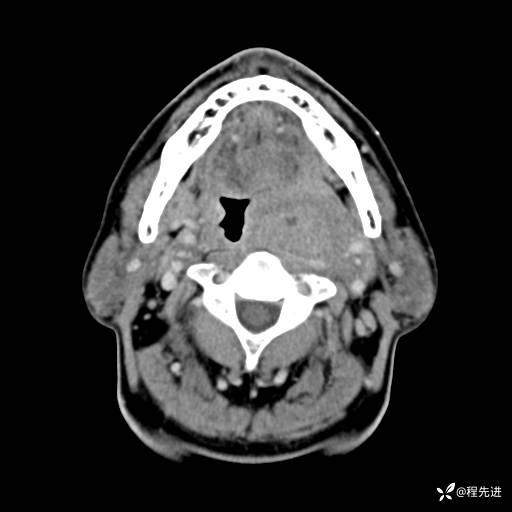

CT增强:

动脉期:

静脉期:

增强冠矢状位重建: